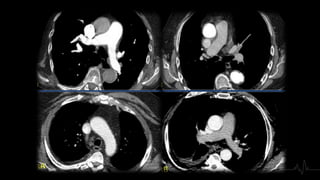

1. REPLECIÓN

Localización en el vaso

Morfología

Ángulo con respecto a la luz

2. TIPO DE TROMBO

Trombos Agudos

Localizados - centro

de la luz del vaso

Provocan dilatación Ocupan la totalidad de

la luz

Paso de contraste en

la periferia

Trombo rodeado de

contraste

(Signo de tranvía) Localización

excéntrica

Presentan ángulo

agudo con la luz del

vaso

Trombo Crónico

Defecto de

repleción completo

Disminución de

calibre y atrofia

vascular

repleción parcial

Localizarse en la

periferia del vaso

A veces son

concéntricos

Morfología de

banda lineal, red o

trombo mural

excéntrico

Calcificación del

trombo

Aumento de calibre

de las arterias

bronquiales y

colaterales

Menos frecuente

dilatación

segmentaria

bronquial

Localización en elvaso Morfología Ángulo con respecto a la luz 2. TIPO DE TROMBO

Trombos Agudos Localizados -centro de la luz del vaso Provocan dilatación Ocupan la totalidad de la luz Paso de contraste en la periferia Trombo rodeado de contraste (Signo de tranvía) Localización excéntrica Presentan ángulo agudo con la luz del vaso

Trombo Crónico Defecto de replecióncompleto Disminución de calibre y atrofia vascular Defecto de repleción parcial Localizarse en la periferia del vaso A veces son concéntricos Morfología de banda lineal, red o trombo mural excéntrico Calcificación del trombo Aumento de calibre de las arterias bronquiales y colaterales Menos frecuente dilatación segmentaria bronquial